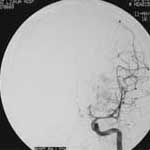

一、颅内动脉瘤

----对颅内动脉瘤的介入治疗主要分为载瘤动脉闭塞和选择性动脉瘤栓塞两种。对于颈内动脉岩部或海绵窦段以及后循环的梭形或宽颈动脉瘤,在代偿试验良好的情况下,可以闭塞载瘤动脉。半年后动脉瘤可逐渐皱缩吸收,明显减少压迫效应。如侧支循环代偿不足,则应先行颅内外动脉架桥。选择性动脉瘤内栓塞主要适用于瘤颈清楚、后循环动脉瘤、多次SAH、HH分级偏高,有血管痉挛或手术风险较大的患者。 近年来,由于显微导管和栓塞材料的可控制研制,使得颅内动脉瘤的血管内栓塞治疗越来越普遍。在欧洲,几乎占所有治疗动脉瘤的80%。栓塞材料主要由Guglielmi等发明的电解脱铂金弹簧圈(GDC)为先导,使动脉瘤的栓塞可以控制释放弹簧圈,进出自由,大大增加了安全性和载瘤动脉的保留。经栓塞后的患者通常2~3天即可出院。尤其对于后循环或巨大动脉瘤等手术难以接近或无法夹闭的动脉瘤,栓塞更是独辟蹊径,是手术治疗盲区的重要补充。